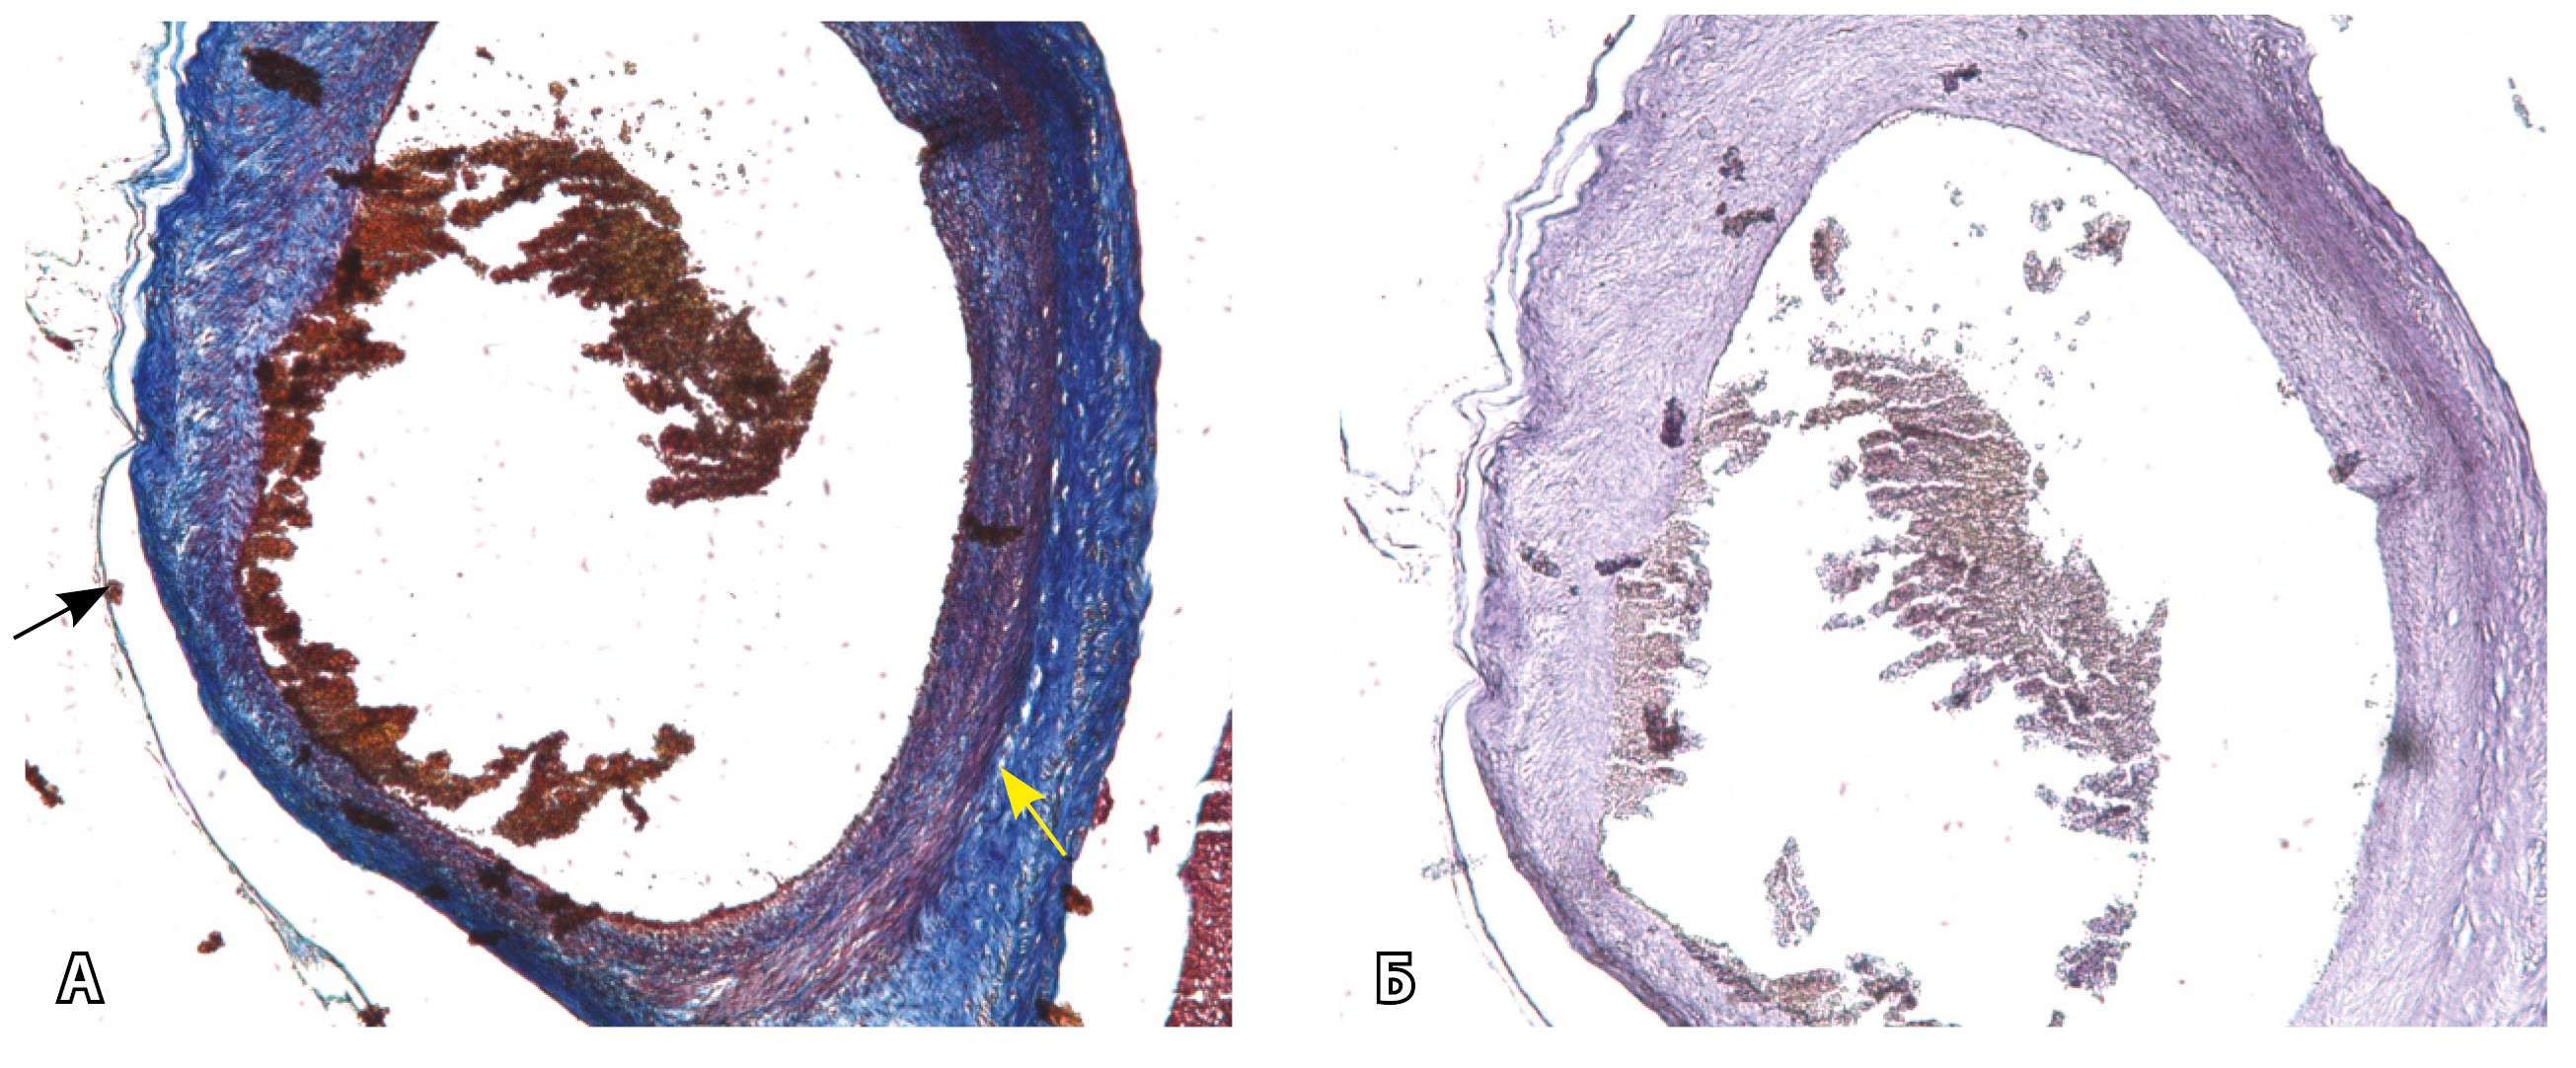

Сосуды 5-го типа. Наличие гиперваскуляризации за пределами матки по данным МРТ, на границе с мочевым пузырем с вовлечением его стенки, сосуды в области перешейка матки, параметрия, в том числе в сочетании с признаками фиброза, наличием рубцово-спаечных изменений и др. Можно предположить, что сосуды 5-го типа являются аналогом pl. рercreta PAS 3b, 3c (рис. 15).

Рис. 15. Беременность 34 недели, pl. percreta, PAS 3b по FIGO (A, Б), PAS 3c по FIGO (В). На магнитно-резонансных томограммах в режиме Т2-взвешенного изображения в сагиттальной (A, В) и аксиальной (Б) плоскостях определяется гиперваскуляризация в области выраженно истонченного нижнего маточного сегмента с распространением сосудов на заднюю стенку мочевого пузыря в области дна (белые стрелки), в область перешейка матки (желтые стрелки)

Данный вариант в патоморфологической картине наиболее сложен для оценки ввиду того, что такие структуры, как параметрий, перешеек матки, стенка мочевого пузыря, обычно не предоставляются в виде макропрепаратов, поэтому визуальные методы, в частности МРТ, могут с большей точностью оценить вовлеченность смежных структур. На микропрепаратах данный вариант инвазии плаценты сочетается с рубцово-спаечными изменениями задней стенки мочевого пузыря с нижним маточным сегментом (рис. 16).